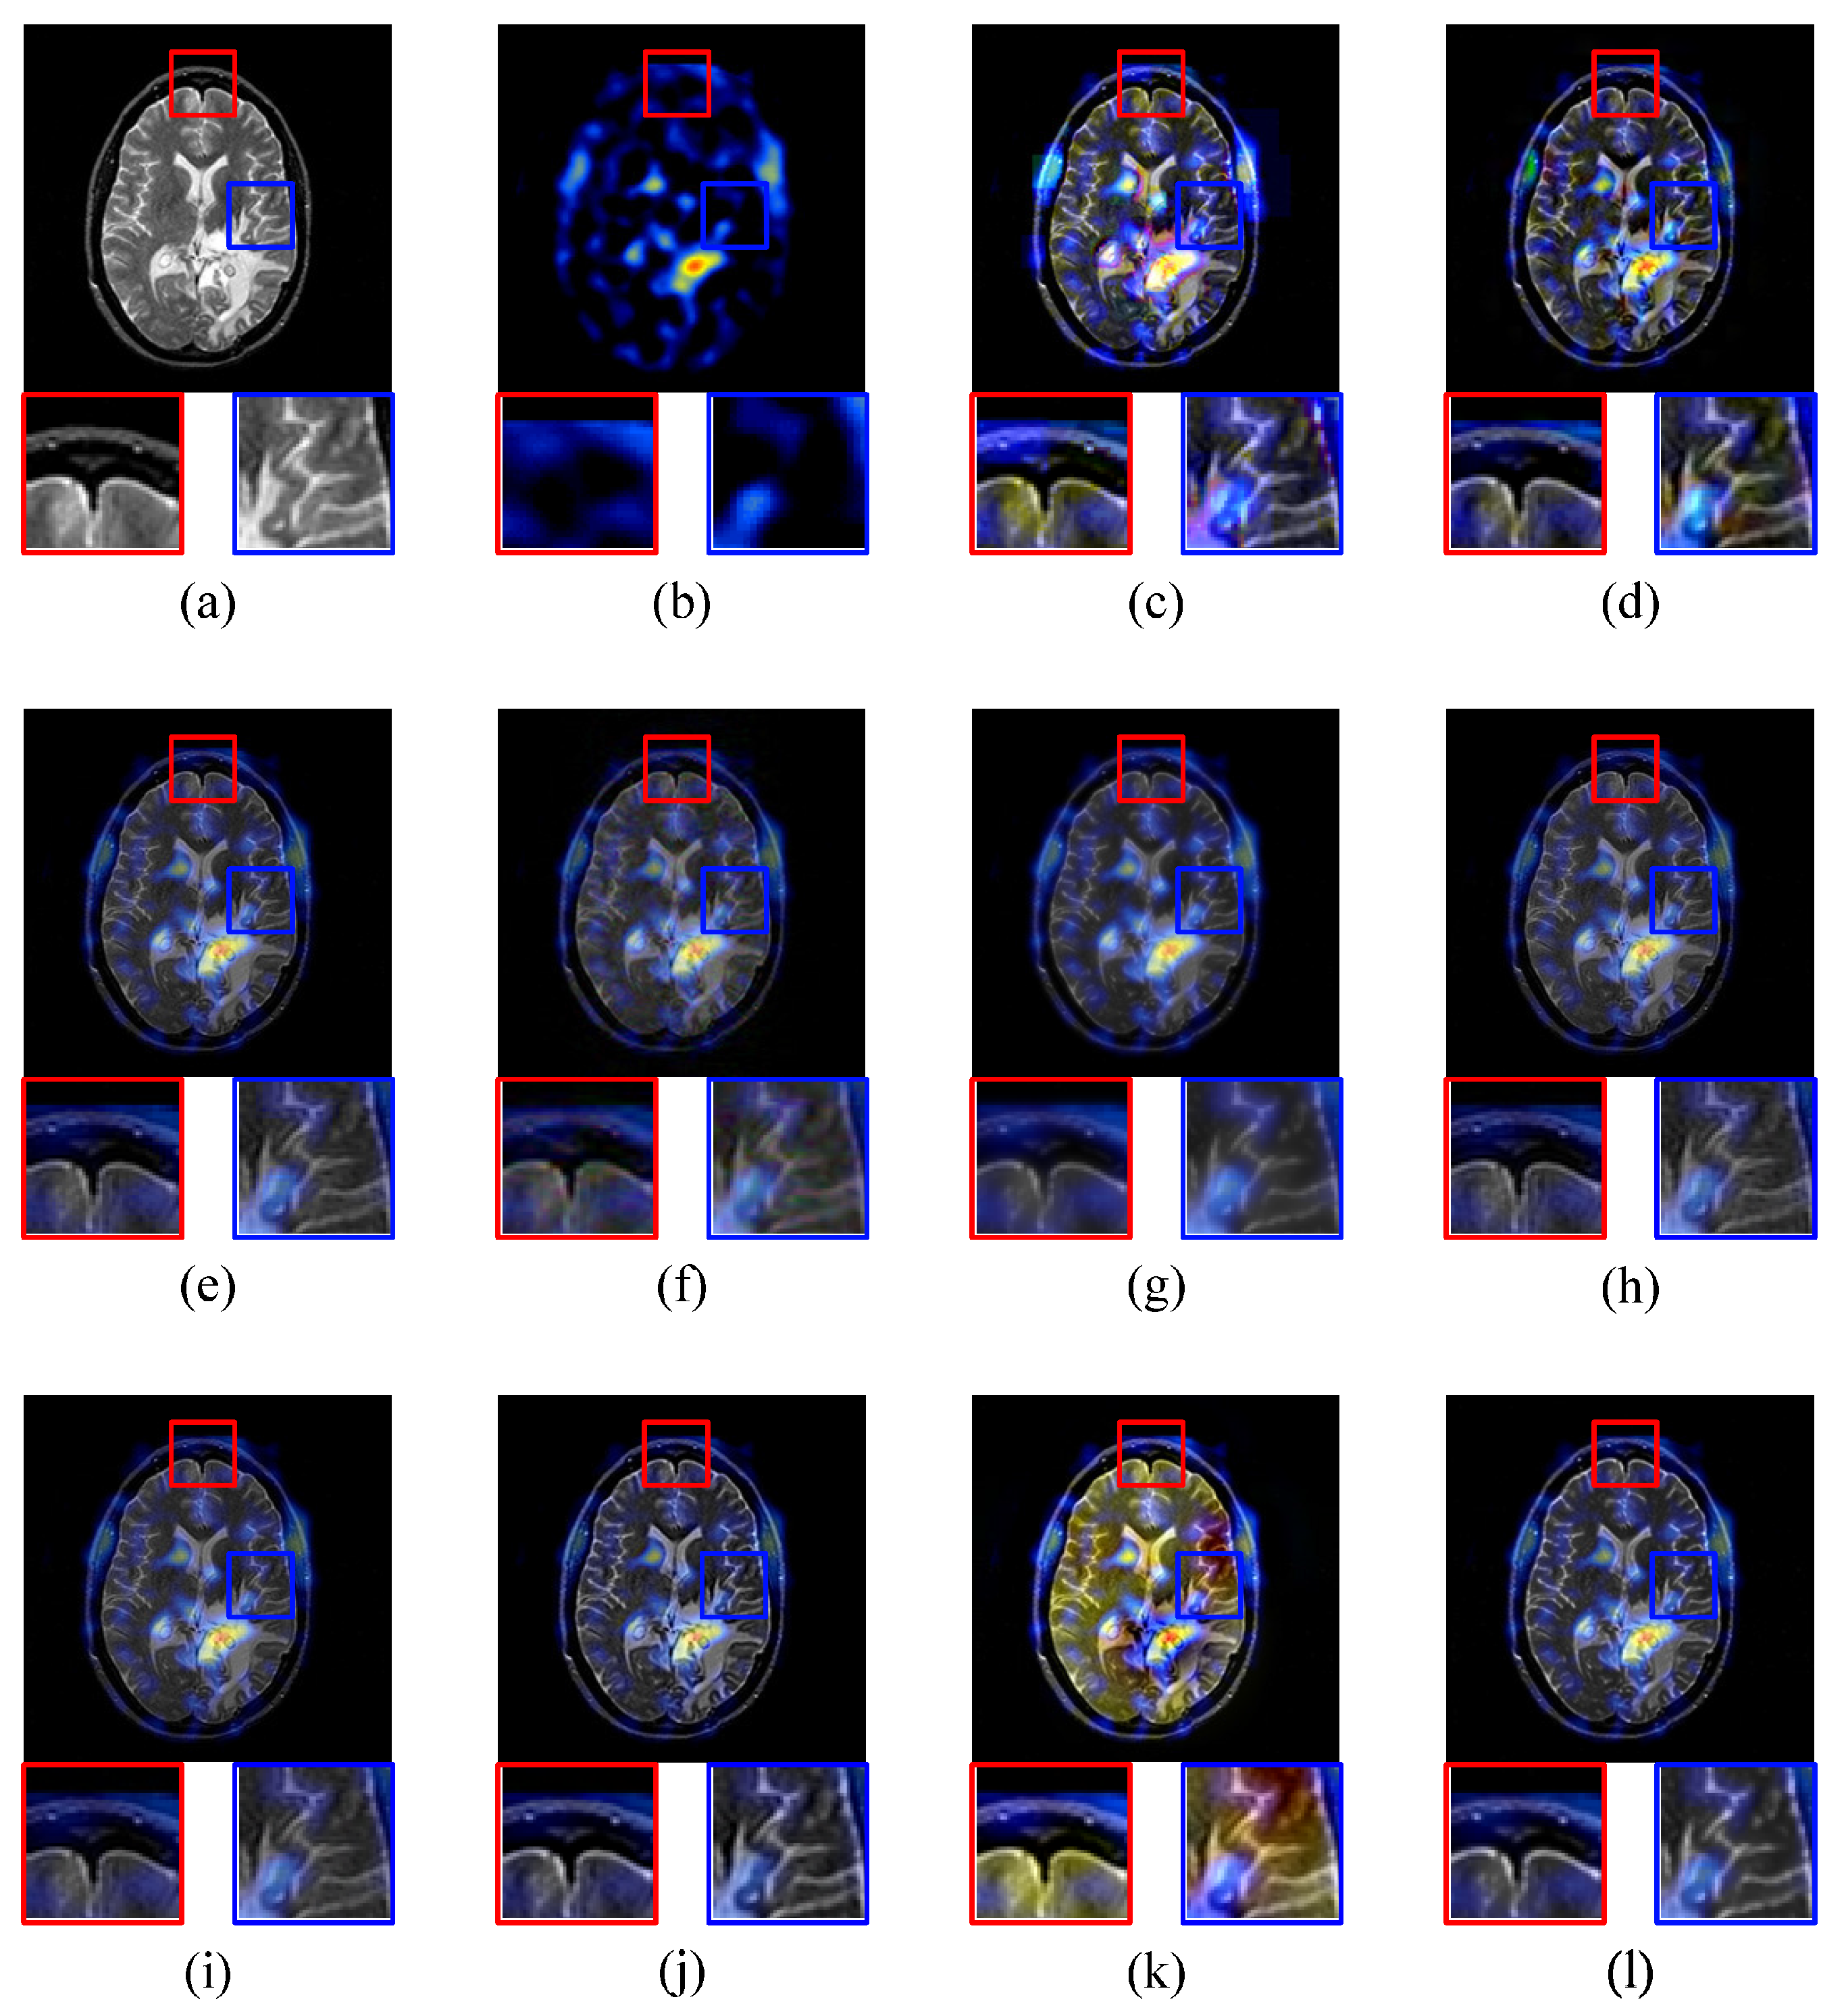

4.2.3. MRI-SPECT Image Fusion Comparative Experiments